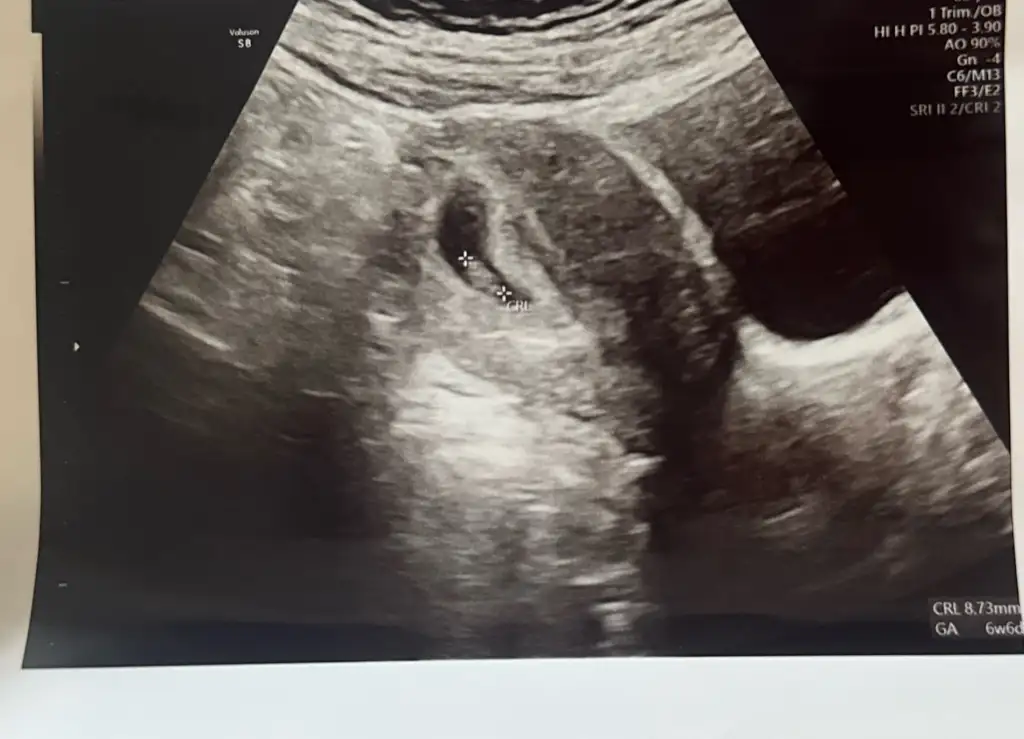

Maşallah. Rahat bir gebelik geçireceksiniz demek kiHiç belirtim yoktu göğüs hassasiyeti haricinde heralde oluşmadı diye korka korka gittim doktora ama çok şükür kalbide yeni atmaya başlamış azda olsa duyabildik 6+6Eki Görüntüle 3619184

MasAllahHiç belirtim yoktu göğüs hassasiyeti haricinde heralde oluşmadı diye korka korka gittim doktora ama çok şükür kalbide yeni atmaya başlamış azda olsa duyabildik 6+6Eki Görüntüle 3619184

Benim 6+6 bugün itibariyle 7 hafta bitmiş oluyor. Bende göğüs hassasiyeti dışında belirti yok. Ara sıra çok nadir kasık ağrısı gibi bir his o kadar. Hatta bugün kalp atışını duyana kadar çok endişeliydim neden belirtim yok oluşmadı mı acaba diye korka korka gittim doktora. Daha önce kayıplarım var insan ister istemez endişe ediyor.Ay 6. Hafta herkes kötü olmuş haftaya beni neler bekliyor bakalım

Erkek bebek kesesi fasulye gibi derler, doğru mu acaba sizinle takip edelim bakalım doğru muymuş. Kesesi çok net naşallahHiç belirtim yoktu göğüs hassasiyeti haricinde heralde oluşmadı diye korka korka gittim doktora ama çok şükür kalbide yeni atmaya başlamış azda olsa duyabildik 6+6Eki Görüntüle 3619184